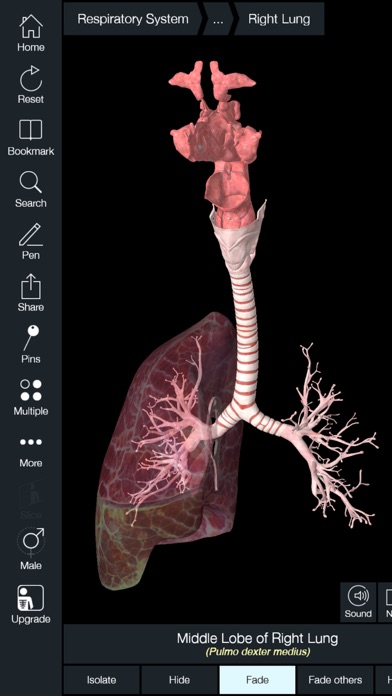

Essential Anatomy 5 IPA MOD IOS is a revolutionary app that has changed the way we learn about the human body. With its advanced features and stunning visuals, this app provides an immersive and interactive experience for users. Whether you are a medical student, healthcare professional, or simply interested in learning about anatomy, Essential Anatomy 5 is a must-have tool. It offers a comprehensive library of detailed 3D models, allowing users to explore every aspect of the human body. From the skeletal system to the muscular system, nervous system to cardiovascular system, this app covers it all. Additionally, it provides in-depth information on each structure, including names, functions, and clinical relevance. With its user-friendly interface and intuitive controls, navigating through the app is a breeze. Overall, Essential Anatomy 5 IPA MOD IOS is an essential resource that brings anatomy to life, making it an invaluable tool for anyone interested in the human body.

This app provides a comprehensive and detailed 3D representation of the human body. With over 8,200 anatomical structures, including muscles, bones, organs, and more, it offers a level of accuracy and depth that is unparalleled. Whether you are studying for an exam or explaining a medical condition to a patient, Essential Anatomy 5 IPA has the information you need.

Essential Anatomy 5 IPA allows users to interact with the 3D models, zooming in and rotating them to explore every angle. The user-friendly interface makes navigating through the app a breeze, and the intuitive controls ensure that anyone, regardless of their level of expertise, can easily explore and understand the complex anatomical structures.

One of the standout features of Essential Anatomy 5 IPA is its ability to showcase cross-sectional views of the body. This enables users to see the internal structures and their relationships with each other, providing a deeper understanding of the body’s intricate systems. This feature is particularly useful for students learning about the different body cavities or professionals wanting to explain surgical procedures to their patients.

Essential Anatomy 5 IPA is constantly updated with new content, improvements, and bug fixes. This ensures that you always have access to the latest information and technological advancements in the field of anatomy. By regularly updating the app, the developers show their commitment to providing users with the best possible learning experience.